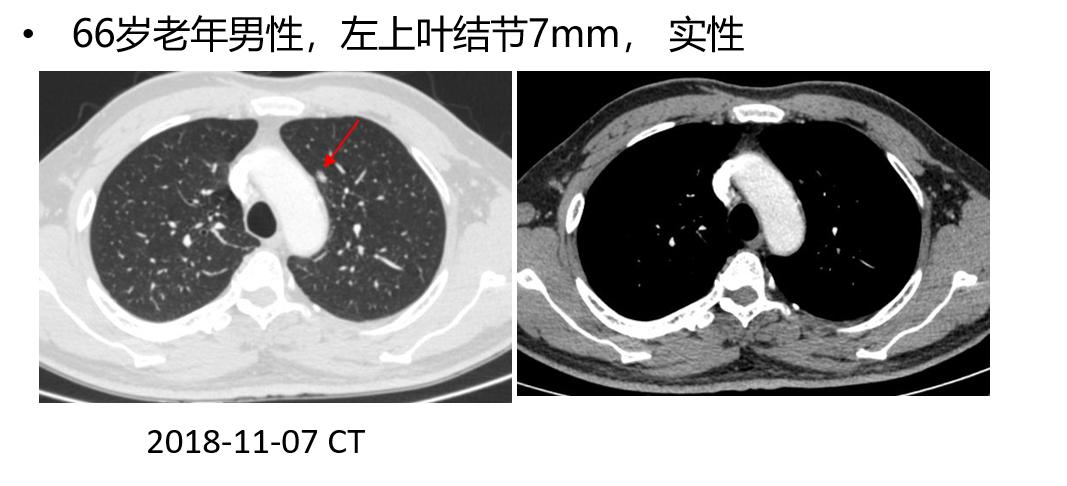

ENB引导下注射ICG胸腔镜术前肺微小病变定位